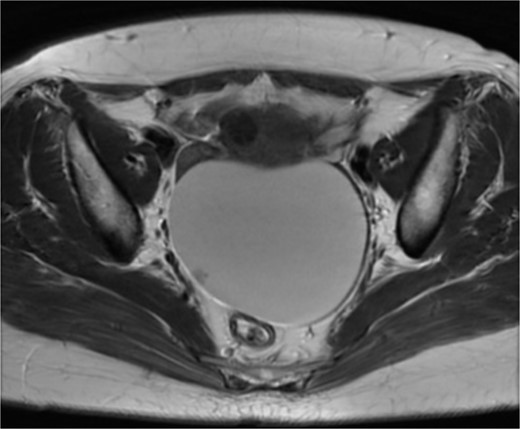

On admission, the patient was found to have a soft tumor, 10 cm in size, in her lower abdomen. She didn’t feel any tenderness at the site of the tumor. Abdominal ultrasonography showed a cystic mass with a small solid portion with a clear margin. Her serum levels of CA125, CA19-9, and carcinoembryonic antigen (CEA) were within normal limits. Computed tomography (CT) scan revealed a 10 cm sized cystic mass (Fig. 1). Magnetic resonance imaging (MRI) also revealed a 10 cm sized cystic mass with a solid part in the pelvis (Fig. 2).

Magnetic resonance imaging: 10 cm sized cystic mass a solid part (arrow) in the pelvis.